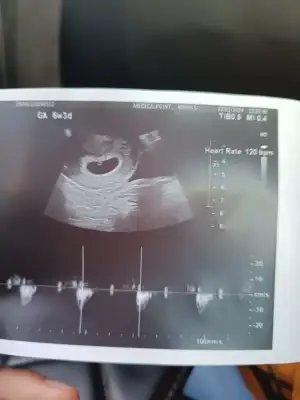

7+0 keseden cinsiyet tahmin edebilir misiniz 🙈

Merhaba, daha çok ufağız ama ilk gebeliğim olduğu için heyecanlı ve sabırsızım 🥰

Vajinal ultrasonla 7+0 da bakıldı. Keseye göre tahminde bulunabilir misiniz 🙏